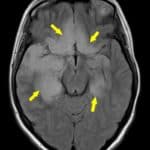

Viêm Não | Bài giảng CĐHA

Viêm não là tình trạng viêm của nhu mô não, biểu hiện bằng sự rối loạn chức năng thần kinh-tâm thần khu trú hoặc lan tỏa. Đây là một tình trạng bệnh lý nặng nề đe dọa tính mạng bệnh nhân. Viêm não có thể biểu hiện dưới hai thể khác nhau: thể tiên phát và thể thứ phát. Viêm não tiên phát thường nặng nề hơn trong khi viêm não thứ phát thường gặp hơn. Tuy nhiên do thể thứ phát thường nhẹ nhàng hơn nên trong số các trường hợp nhập viện, viêm não tiên phát chiếm đa số…